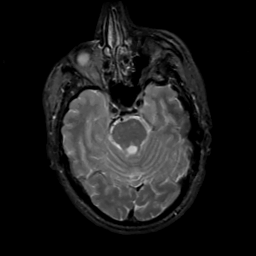

MR Study #5, March 10, 1991 -- Slice #17